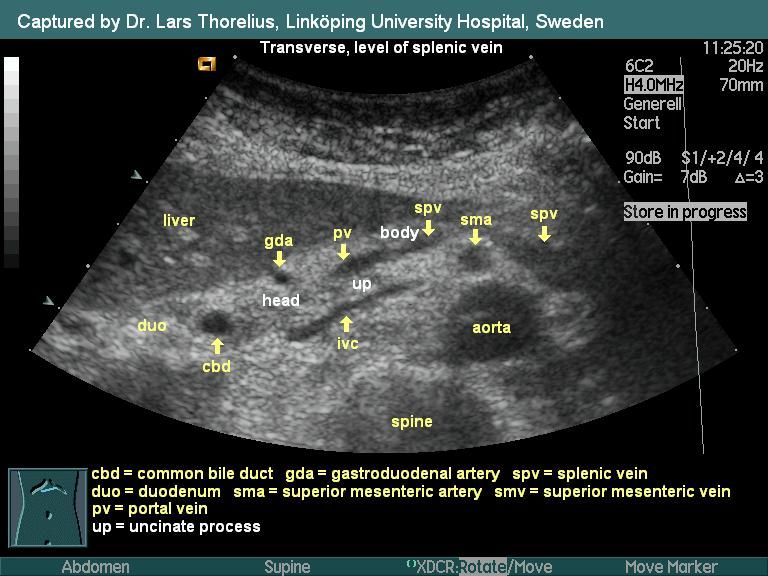

- Ultrasound: This non-invasive method uses sound waves to create real-time images of the spleen and other abdominal organs.

Among these imaging techniques, abdominal ultrasound is often the preferred method for evaluating spleen size due to its accessibility, lack of radiation exposure, and ability to provide accurate measurements.

Ultrasonography: The Gold Standard for Spleen Measurement

Abdominal ultrasonography has emerged as the gold standard for assessing spleen size due to its numerous advantages. This non-invasive imaging technique offers real-time visualization of the spleen and surrounding structures, allowing for accurate measurements and detection of abnormalities.

During an ultrasound examination of the spleen, a trained sonographer or radiologist uses a handheld transducer to send high-frequency sound waves through the abdominal wall. These sound waves bounce off the internal organs, including the spleen, and return to the transducer, creating detailed images on a computer screen.

Spleen Measurement Techniques

Ultrasound allows for precise measurements of the spleen’s dimensions, including:

- Length: Measured along the organ’s longest axis

- Width: Taken at the widest point perpendicular to the length

- Thickness: Measured from the anterior to posterior surface

These measurements provide a comprehensive assessment of spleen size and shape, enabling healthcare providers to identify any abnormalities or enlargement accurately.

An abdominal ultrasound is often preferred for evaluating the spleen because it’s easy to do and doesn’t require any radiation. Ultrasound uses sound waves to create images of inside the body on a computer screen. An ultrasound “wand” is rubbed on the outside of the belly, which is coated with a special gel. This gel helps transmit the sound waves through the skin and to the parts inside the body.

Ultrasound can usually measure the length of the spleen along a center line (axis) accurately. It can also measure the width and thickness of the spleen, which can typically tell the doctor whether the organ is abnormally large or small. In most cases, however, the concern is about an enlarged spleen.

The specialist analyzes the position of the spleen relative to other organs: a healthy spleen is located on the left, at the top of the abdominal cavity, and the stomach is located in the middle of the spleen. During an ultrasound examination, it is important to pay attention to details: the diameter of the splenic vein of a healthy organ cannot be more than 1.5 cm, the echostructure of a healthy spleen must be homogeneous. Identified deviations are recorded in the conclusion. Subsequently, the doctor, based on the data obtained, makes a diagnosis and prescribes treatment.